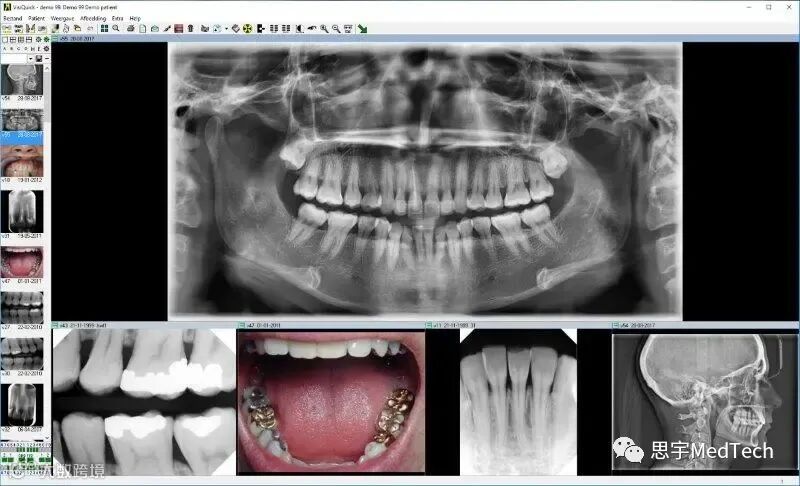

VisiQuick/Citodent Imaging 的总监Piet Reijers介绍了VisiQuick软件的功能和特点。他说:“VisiQuick软件是一个全面的牙科影像软件,它可以让牙医方便地获取、查看、增强、比较和注释所有X光片和口腔图像,从而优化牙科工作流程和简化患者管理。

VisiQuick软件还支持所有类型的数字影像设备,包括数字传感器、扫描仪、数字全景设备、数字相机、成像板系统和视频源。用户可以根据自己的需要选择合适的硬件,而不受影像软件供应商的限制。用户也不必为每个影像设备学习不同的软件应用程序,因为VisiQuick软件可以统一管理所有的影像信息。”

他还说:“VisiQuick软件不仅可以获取和查看影像,还可以提供多种图像增强功能以及注释工具,帮助用户完成日常工作。VisiQuick软件还具有灵活的网络功能,可以在局域网、云端或终端服务器环境中运行。当用户想要查看或获取新的影像时,VisiQuick软件会自动与用户的患者管理程序对接,调出当前患者的信息。用户还可以从网络中的任何地方打开患者文件,实现远程访问和共享。”

VisiQuick是一个牙科影像软件,它可以帮助牙医获取、查看、增强、比较和注释所有类型的牙科图像,包括X光片、口腔图像、彩色图像和文档。

VisiQuick可以与所有数字传感器、扫描仪、数字全景设备、数字相机、成像板系统和视频源兼容。其优点是用户可以自由选择自己想要使用的硬件,而不受影像软件供应商的限制。用户也不需要为每个影像设备学习不同的软件应用程序,因为VisiQuick可以统一管理所有的影像信息。

VisiQuick还提供了多种图像增强功能以及注释工具,以协助用户完成日常工作。VisiQuick可以在局域网、云端或终端服务器环境中运行,还可以与患者管理程序自动对接,当用户想要查看或获取新的影像时,VisiQuick会自动调出当前患者的信息。用户还可以从网络中的任何地方打开患者文件,实现远程访问和共享。